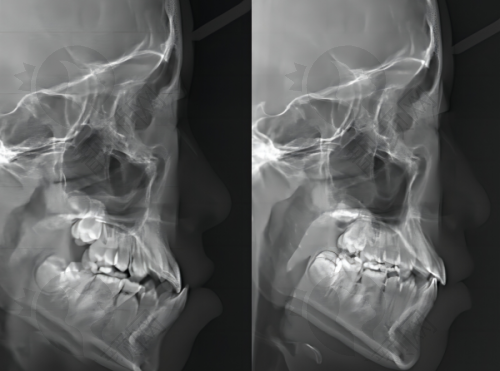

数字化口腔扫描和计算机辅助设计与导航系统更是让种植牙手术变得更加精细。数字化口腔扫描能够快速、正确地获取患者口腔的详细数据,医生可以根据这些数据进行计算机辅助设计,制定出更适合患者的种植方案。在手术过程中,导航系统可以引导医生严谨地将种植体植入到预定的位置,提高了种植体的稳定性和成功几率。

特别是医院擅长的all - on - 4/6全口种植技术,这可是解决复杂牙齿缺失问题的“利器”。对于那些牙齿缺失重度、骨量不足的患者来说,传统的种植方法可能比较困难。而all - on - 4/6全口种植技术通过精密定位、少量植体、即刻修复的方式,不仅解决了这些复杂病例,还大大缩短了治疗周期,减少了患者的痛苦和术后改善时间。